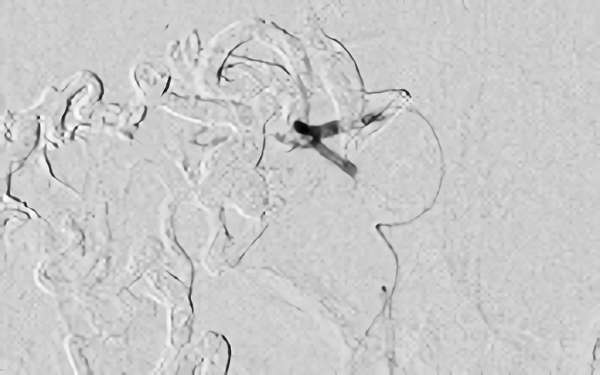

'24年8月

左前頭葉脳動静脈奇形

10代

秋田県の病院

No.1494 手術後